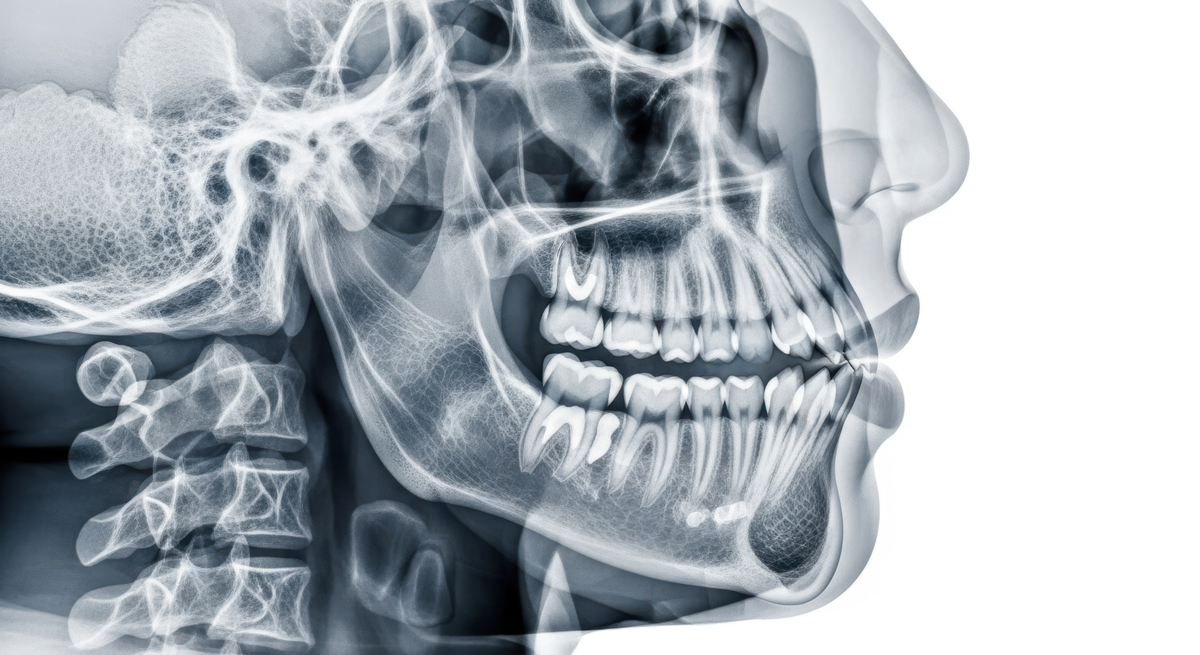

Corrective jaw surgery, also known asorthognathic surgery, repositions the upper jaw, lower jaw, or both to improve how your teeth and jaws work together. The results can be life-changing, affecting everything from how you eat and speak to how you sleep and breathe.

Ouroral and maxillofacial surgery team treats jaw alignment problems that braces alone simply cannot resolve. When the upper and lower jaws grow at different rates, or when a birth defect or facial injury affects jaw structure, surgery becomes the most effective path to lasting relief. The goal is always a healthy, balanced, and pain-free bite that holds up for life. There are several types of surgeries available depending on your anatomy and goals, and our team will identify the right approach for your unique situation during a thorough consultation.